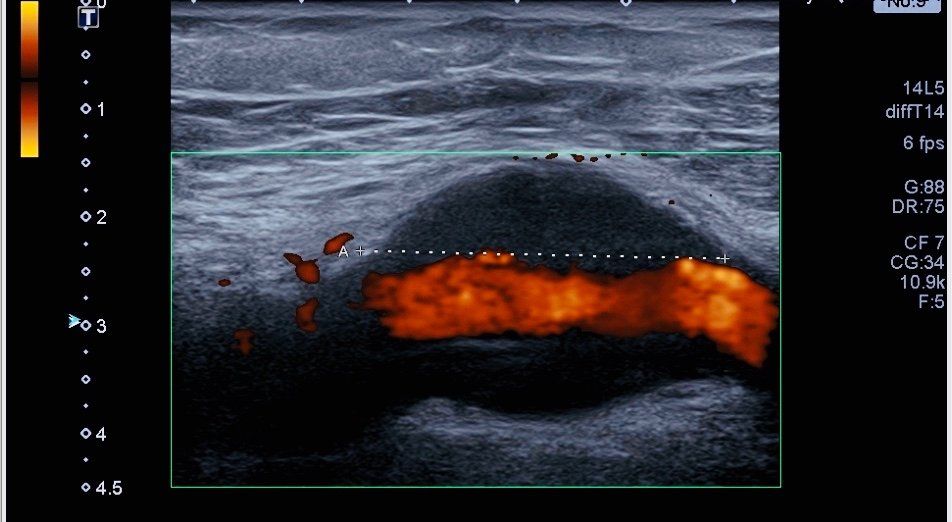

Une échographie musculo-squelettique est souvent nécessaire à l'établissement d'un diagnostic précis en cas de pathologies musculaires ou tendineuses. Le Dr Le Masle-Lastiolas est médecin échographiste spécialisé dans le diagnostic et la prise en charge de ces pathologies. Le centre Arthrosport-Argonay est équipé d'un échographe précis Canon Aplio Platinium ® permettant la visualisation de pathologies initiales ainsi que le suivi de leur évolution dans le temps.